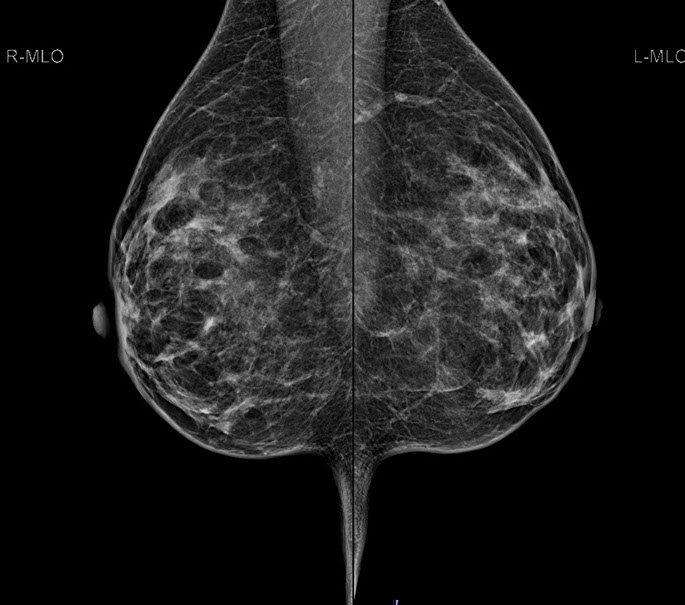

Bei der Mammographie handelt es sich um ein Röntgenverfahren, welches auf einem einfachen Prinzip beruht: Unterschiedliche Gewebestrukturen (Fettgewebe, Bindegewebe, Brustdrüsengewebe) haben eine unterschiedliche Dichte. Die bei der Mammographie verwendete weiche Strahlung wird von einzelnen Gewebekomponenten unterschiedlich absorbiert, woraus unterschiedliche Kontraste im Mammographiebild resultieren.

2.  Bessere Aussagekraft bei dichtem Brustdrüsengewebe

Vor allem junge Frauen bzw. Frauen vor der Menopause haben ein dichtes Brustdrüsengewebe. In der konventionellen Mammographie ließ sich dieses dichte Gewebe oft schlecht darstellen. Aufgrund von Fehlbelichtungen waren Wiederholungsaufnahmen notwendig, die eine zusätzliche Strahlenbelastung mit sich brachten. Die digitale Mammographie kann hingegen auch geringere Kontraste in sehr dichtem Brustdrüsengewebe deutlicher hervorheben und so eine zuverlässigere Diagnostik ermöglichen. Fehlbelichtungen wie bei der alten konventionellen Mammographie werden praktisch ausgeschlossen.

3.  Exaktere Bildanalyse – sicherere Diagnose

Durch die höhere Kontrastauflösung bei einem höheren Kontrast-Rausch-Verhältnis wird die Erkennungsrate von malignitätsverdächtigen Veränderungen deutlich verbessert. Der Radiologe kann auf hochauflösenden 5 MP-Monitoren die Dichte, Form und Kontur von Gewebearealen wesentlich exakter differenzieren und so gutartige von bösartigen Herdbefunden sicherer unterscheiden. Im Speziellen sind Mikroverkalkungen auch bei der dichten Brust besser zu analysieren.

Unter den bildgebenden Verfahren kommt der digitalen Mammographie der höchste Stellenwert zu. Die Mammographie kann häufig Karzinome schon ab einer Größe von wenigen Millimetern entdecken.

Die Diagnosesicherheit und Möglichkeit einer Brustkrebsfrüherkennung durch die Mammographie, hängt von der Dichte des Brustdrüsengewebes ab. Einteilung der Dichtegrade wurde vom American College of Radiology (ACR) übernommen.

Bei einem Dichtegrad 3 sinkt die Sensivität der Mammographie deutlich, bei Dichtegrad 4 liegt sie unter 50 %. Durch gleichzeitigen Einsatz der Ultraschalluntersuchung wird die Sicherheit in der Diagnoseerstellung jedoch wieder auf

ca. 90 % angehoben.

40 % der Mammakarzinome weisen Mikroverkalkungen auf. Mikrokalzifikationen sind auch bei sehr dichtem Brustgewebe immer sichtbar. Eine Mammographie sollte daher ab dem 40. Lebensjahr die primäre Untersuchungsmethode sein.